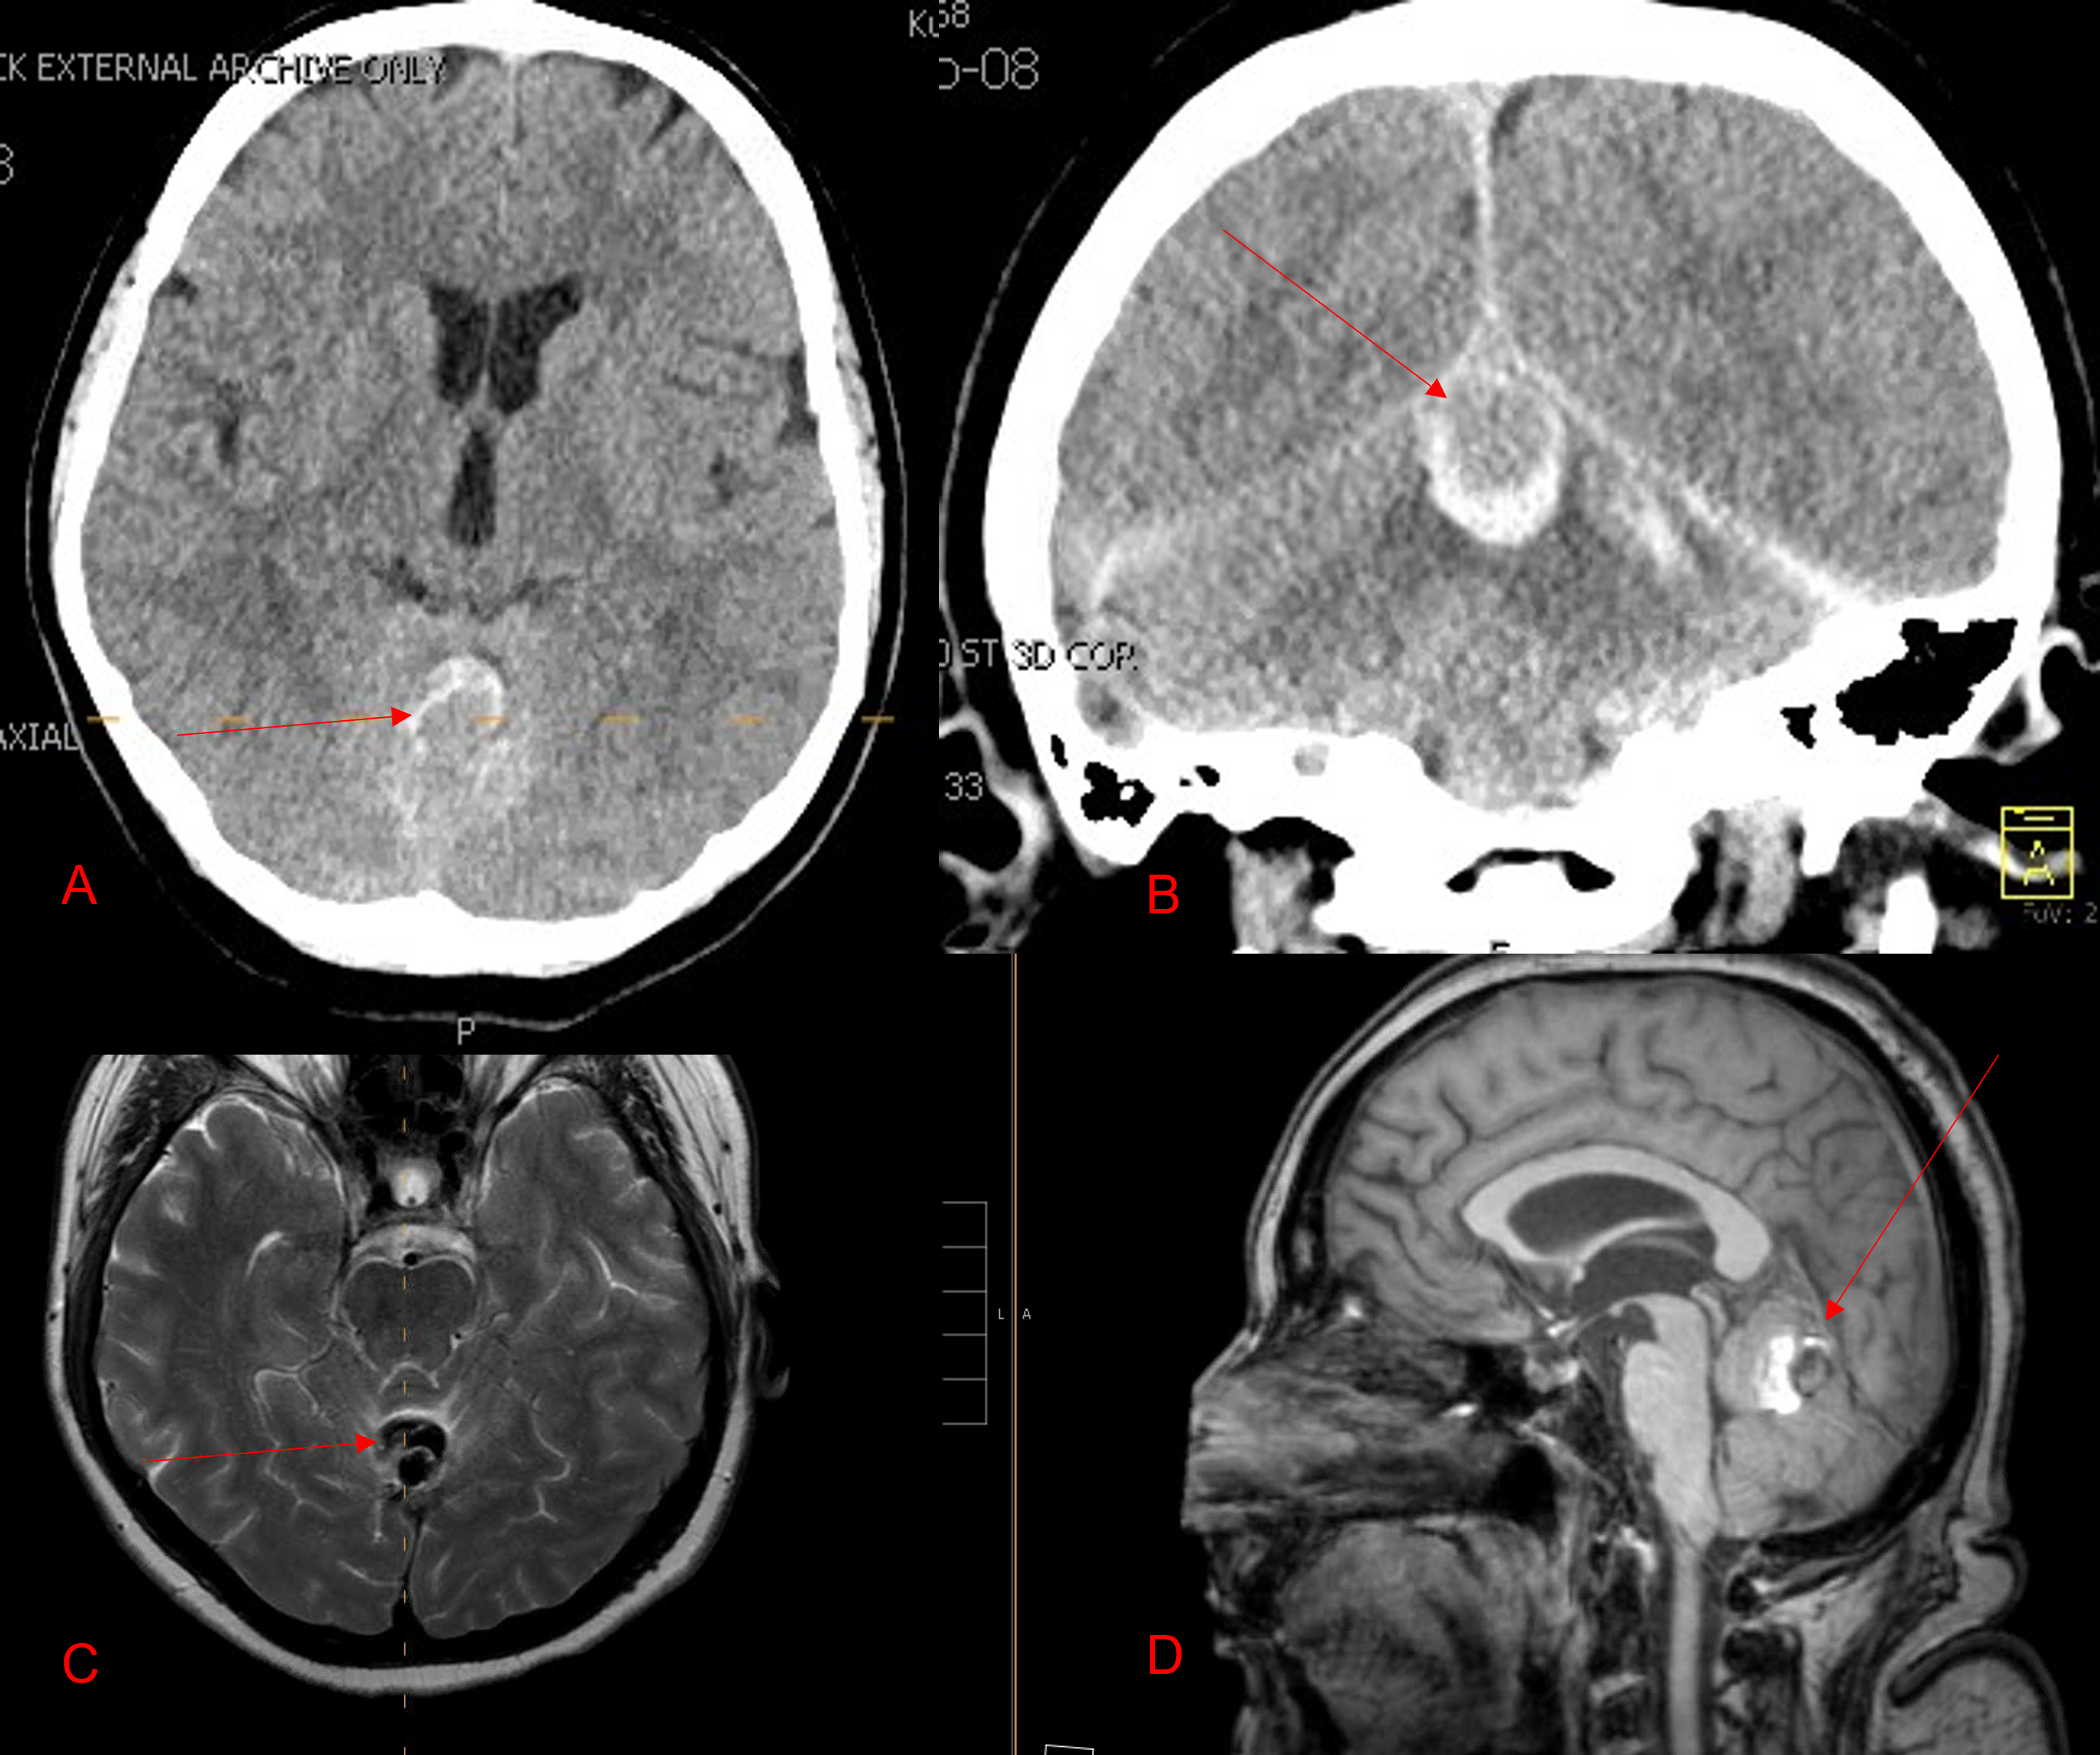

This 59 year-old female had severe bilateral leg pain and numbness over a 6 month period. The patient had failed conservative treatment with physical therapy, chiropractic care, and medications. MRI revealed that she had severe lumbar stenosis with a grade 1 spondylolisthesis or “slipped disc” at L5-S1 (Fig 2).

In addition, she had previously undergone both front and back surgery for severe cervical stenosis where her posterior hardware had failed because of her severe osteoporosis requiring us to remove the posterior hardware . This required her to have an anterior or front operation which allowed better fixation to her spine because of the load-sharing nature of the interbody grafts in addition to her anterior cervical plate (Fig 3).

(Fig 3) Lateral Intraoperative Cervical X-ray demonstrating good alignment after C4-C6 anterior cervical discectomy and interbody fusion with plate. Note the interbody grafts help load share the plate in this patient with severe osteoporosis.